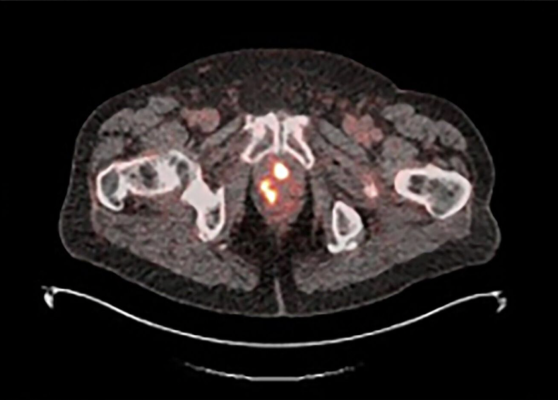

18F-rhPSMA-7.3 PET image showing multiple areas of uptake in the prostate gland in a man with newly diagnosed prostate cancer Photo courtesy of Blue Earth Diagnostics